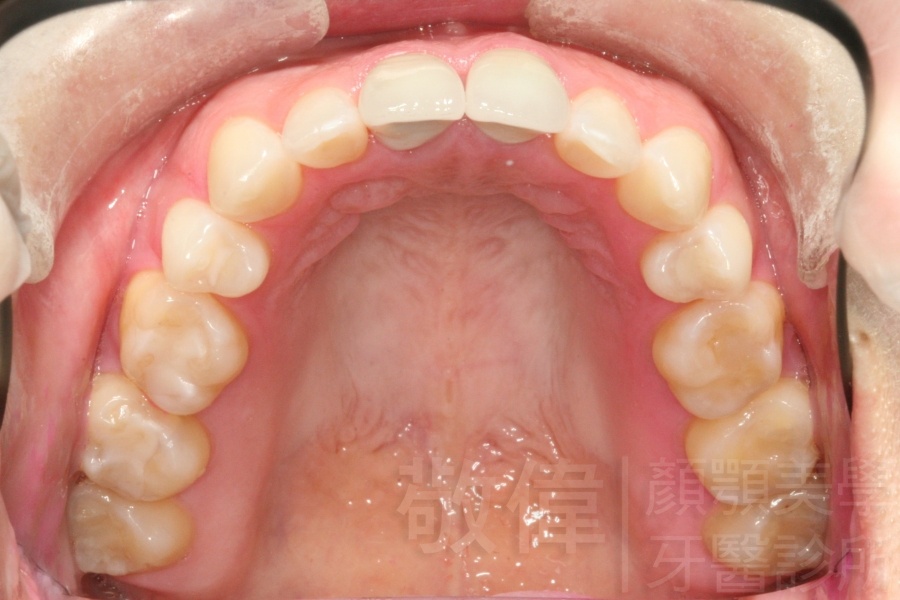

變臉矯正,原來戽斗妹跟大歪臉變成自信正妹

經由本院3D數影X光影像儀分析、與3D齒顎顏矯正技術,再配合口腔顎面正顎專科醫師施以正顎手術治療,雙方共同合作,使患者臉部外觀有很好的改善,大歪變小歪,產生了天南地北的大改變,她的人生也整個變得不一樣。

因為矯正與正顎手術的配合,使「戽斗妹」變成了「陽光正妹」,完全的改變了她的人生,在面對各種場合、與人交際都散發出自信微笑。所以,奉勸家長,如果小朋友有臉顎畸型的問題,應該考慮配合做這種簡單、安全、有效的正顎手術。

「3D齒顎顏矯正」,不止矯正您的牙齒,也會改變您的人生。「治療前」和「治療後」出社會的人生際遇一定會截然不同。